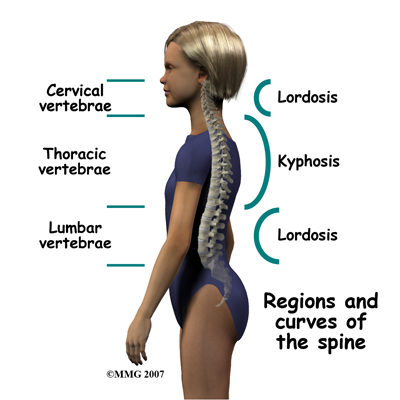

There are three general portions of the spinal column: The cervical or neck portion, the thoracic portion making up the mid-back, and the lumbar or lower portion. The lumbar portion connects with the pelvis at the sacrum.

There are specific curves associated with each region of the spine. When looking from the side, the cervical spine has an inward curve called a lordosis. The thoracic spine curves outward and is called a kyphosis, and the lumbar spine normally curves into the opposite way, creating a lordosis again. These three curves maintain balance of the spine in a forward and backward plane.

When there is a sideways curve in the spine (most exaggerated in the thoracic spine) it is called a scoliosis.